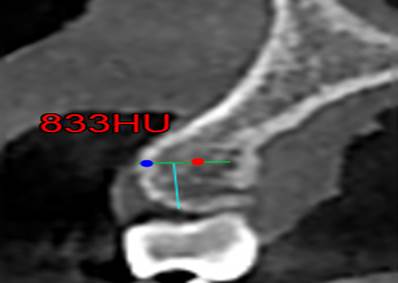

§ Con una profundidad de 0.6 mm a través de la cortical hacia la tabla ósea que es el valor mínimo de un microtornillo ortodóntico en sentido horizontal (imagen 2) interradicular. Las Zonas a medir fueron:

Finalmente se mide las Unidades Hounsfield (UH) a 6 mm intraóseo e interradicular. (Imagen 1,2,3,4).